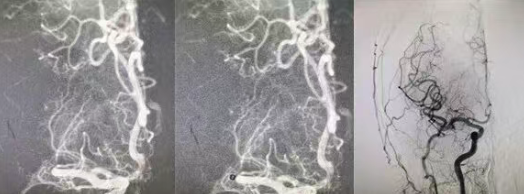

結(jié)合患者癥狀,團隊判斷其為大腦中動脈主干閉塞、大面積血栓,單純?nèi)芩y以徹底打通血管,當(dāng)即果斷制定溶栓后橋接血管內(nèi)拉栓的最優(yōu)救治方案。在溶栓起效的黃金窗口期,醫(yī)護人員迅速將患者轉(zhuǎn)入介入手術(shù)室,全力實施血管拉栓手術(shù)。術(shù)中,介入醫(yī)生精準(zhǔn)定位閉塞血管,憑借嫻熟的微創(chuàng)技術(shù),順利取出堵塞血栓,閉塞的大腦中動脈成功再通,腦部血流恢復(fù)通暢,僅用20分鐘便完成了從穿刺到取栓的全部操作。

從患者入院到溶栓完成,再到血管拉栓成功,整個救治過程高效連貫、環(huán)環(huán)相扣,刷新了醫(yī)院急性大面積腦血栓的急救速度。目前,患者生命體征平穩(wěn),左側(cè)肢體功能正逐步恢復(fù),已成功脫離生命危險,順利進入術(shù)后康復(fù)階段。